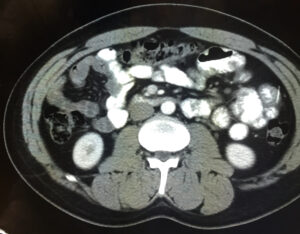

Iatrogenic Bowel Perforation Following Dental Procedure. CT. Unannotated. JETem 2025